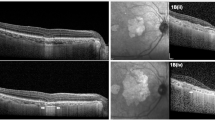

Examples of patients without expert consensus suspected of having other causes of macular atrophy identified in an audit of 1136 cases of macular atrophy Case 21. Classification diagnosis pattern macular dystrophy. Colour fundus photograph of the (A) right and (B) left eyes of a 63 year old white female showing foci of atrophy in the right eye and an incidental left choroidal naevus; OCT scanning of the (C) right and (D) left eyes showing a focus of atrophy in the right eye without drusen; infrared photography of the (E) right and (F) left eyes two years later, at age 65, showing two foci of atrophy with radiating pale lesions in the right eye; FAF of the (G) right and (H) left eyes demonstrating foci of hypoautofluorescence in the right eye. Case 29. Myopic macular atrophy. Infrared images of the (I) right and (J) left eyes; OCT scans of the K) right and L) left eyes of an 87-year-old white male. Images interpreted as showing bilateral peripapillary atrophy, staphyloma and foci of atrophy associated with unrecognized myopic macular changes. Spherical equivalent was R) eye − 1.12D and L) eye − 0.62 pre-cataract surgery.